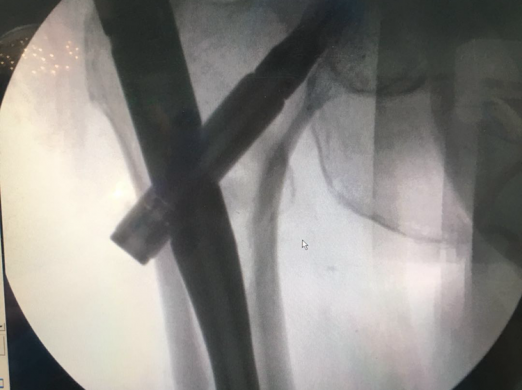

特殊体位下闭合复位微创治疗高龄股骨粗隆间骨折

近日,我院骨伤科顺利为一名83岁高龄的股骨粗隆间骨折患者完成手术。该患者因摔倒致左...